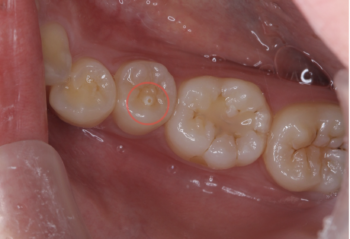

中心結節(ちゅうしんけっせつ)とは、小学校高学年頃に生えてくる大人の歯(永久歯)のうち、特に下顎の第一小臼歯や第二小臼歯に見られる小さな突起状の構造です。発生率はおよそ数%といわれており、決して珍しいものではありません。

この突起は、歯の表面の真ん中やや内側に現れることが多く、外見上は「小さなツノ」や「こぶ」のように見えることもあります。

一見、単なる形の違いのように思われますが、中心結節の内部には歯の神経が通っている場合があるため、そこが折れてしまうと大きなトラブルにつながることがあります。